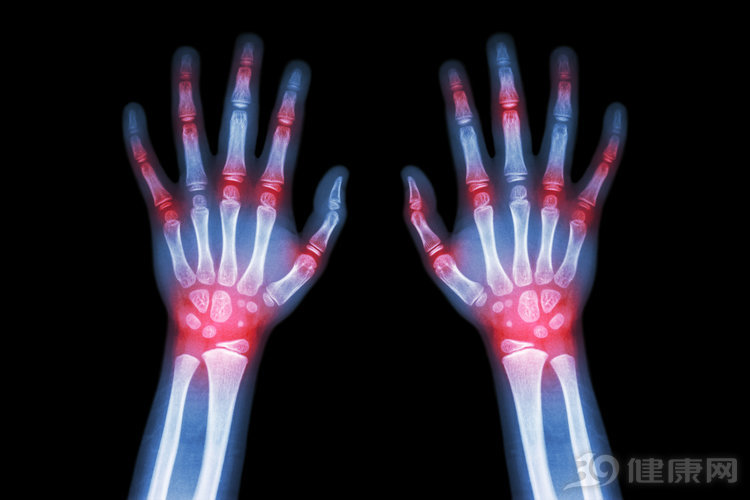

中山大学附属第六医院风湿免疫科黄建林主任细致问诊后,发现他的膝关节特别红肿,便为他安排关节腔穿刺。结果一穿之下,发现吴先生虽然身材比一般人都要壮实,但本应是透明的关节液竟然呈现像牛奶一样的乳白色,显然已经严重变性。

“牛奶状”关节液